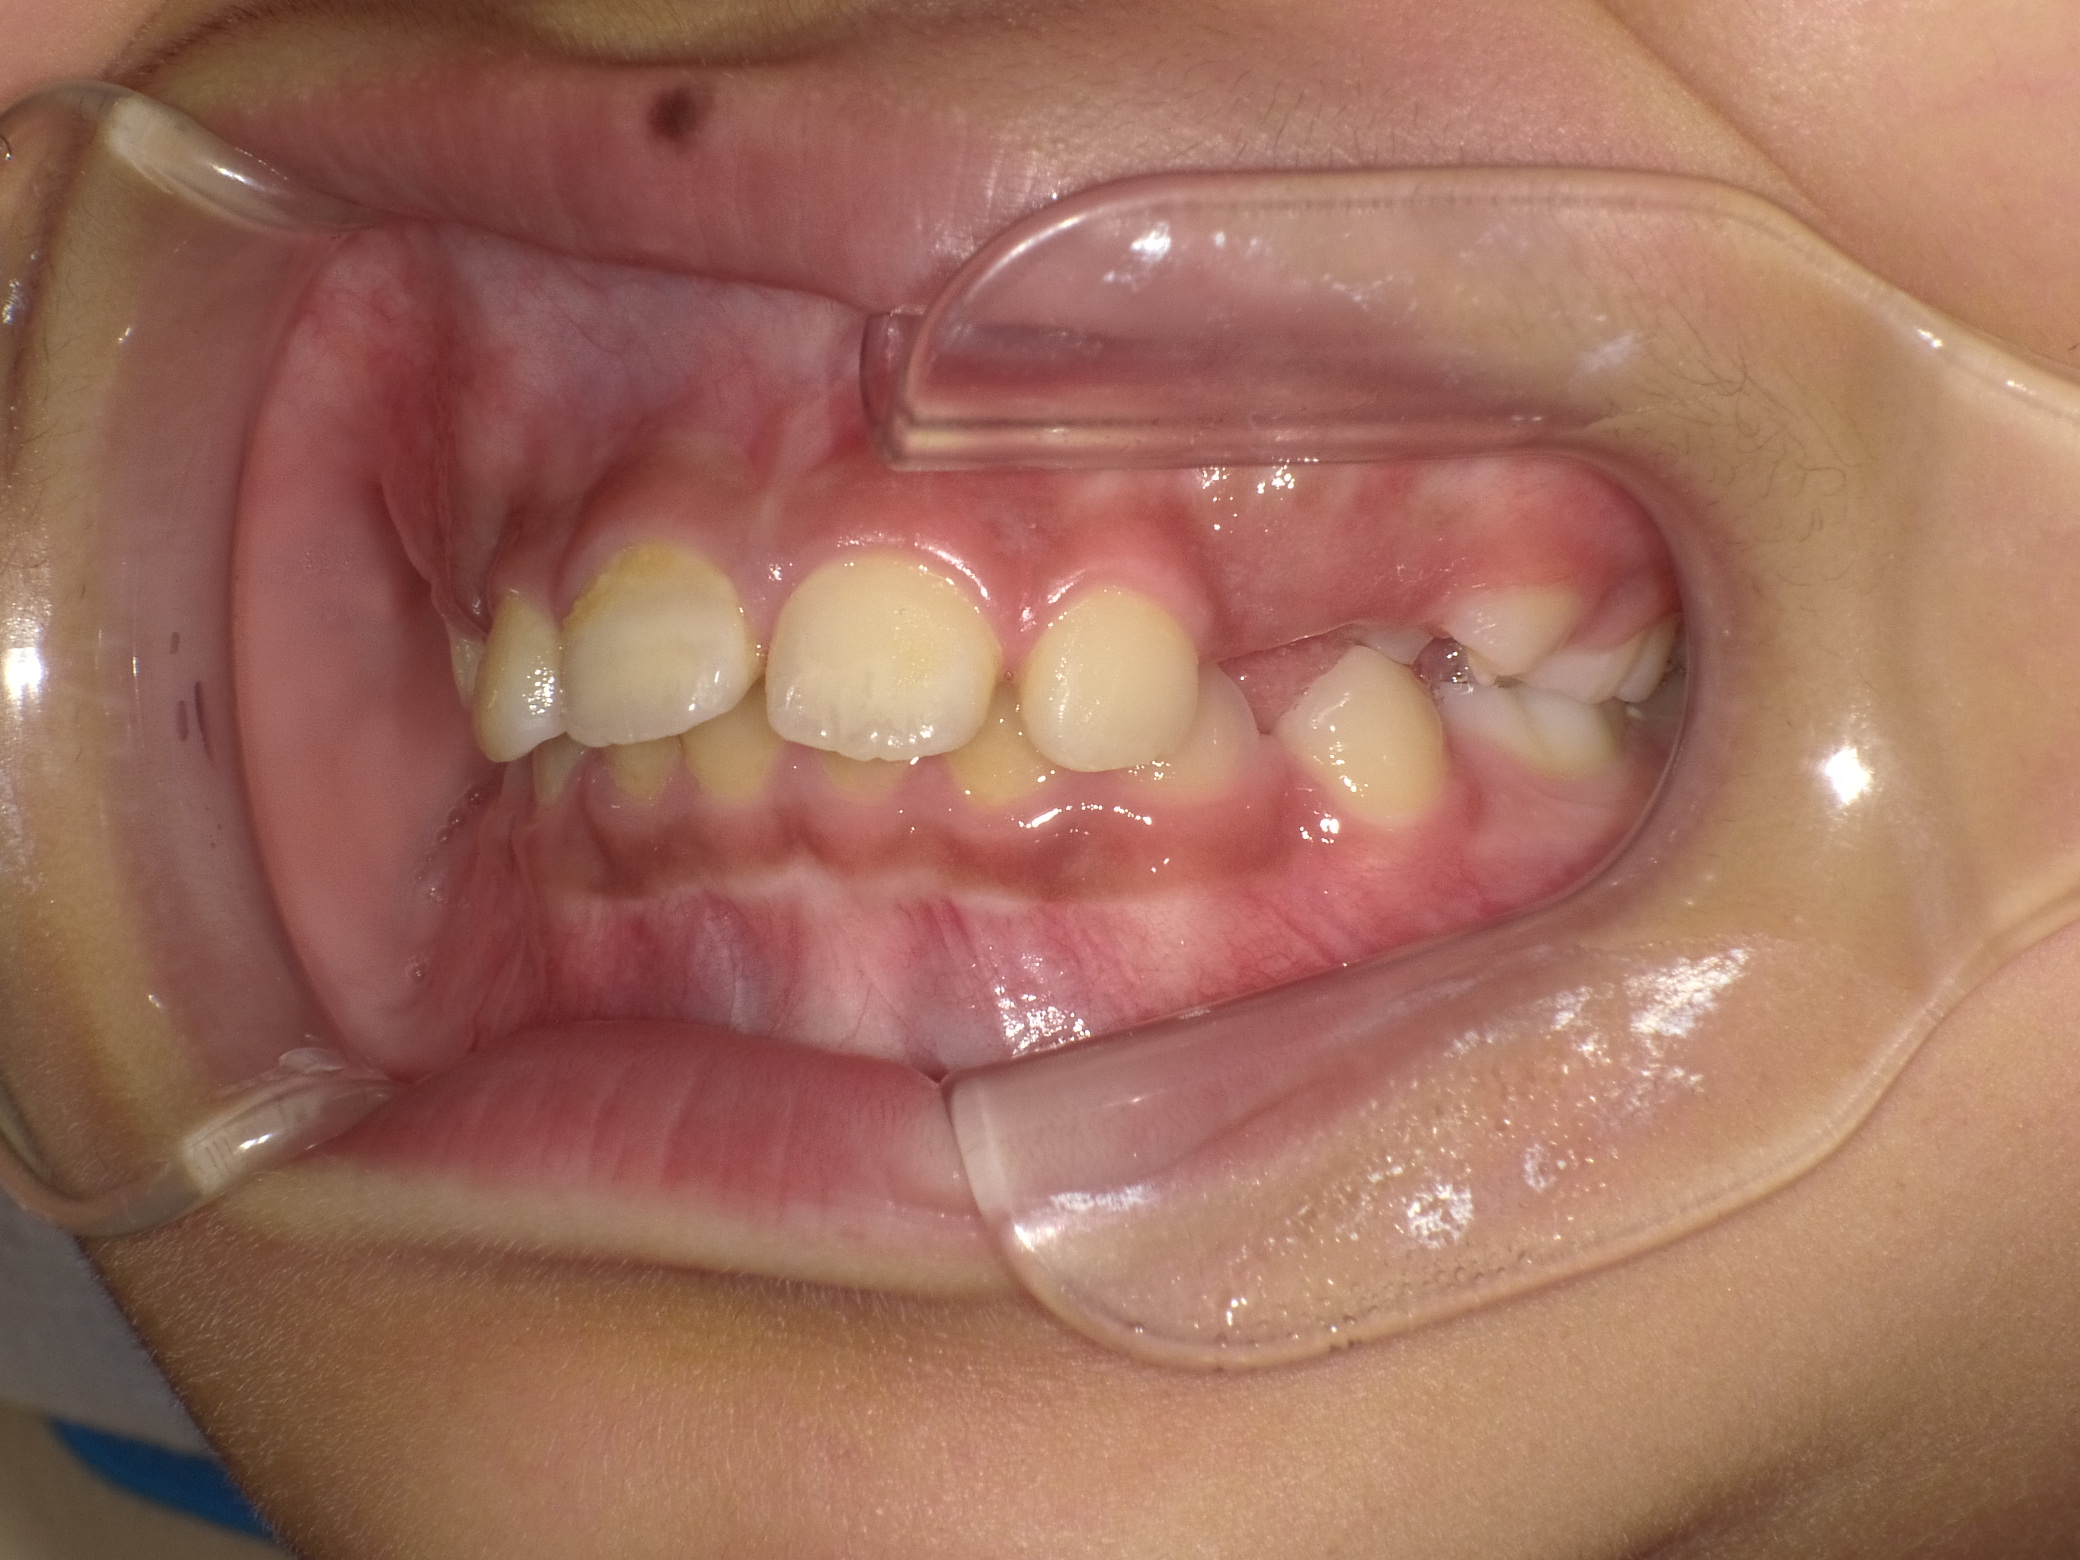

上下顎前突 10歳8ヶ月 男の子

10歳8ヶ月 男子

治療前

お悩み:

口元の突出感(前歯が出ている)と見た目の改善

状態:

骨格:上下あごともに前方に出やすい傾向(上下顎前突)

歯並び:前歯の前方への突出(出っ歯傾向)